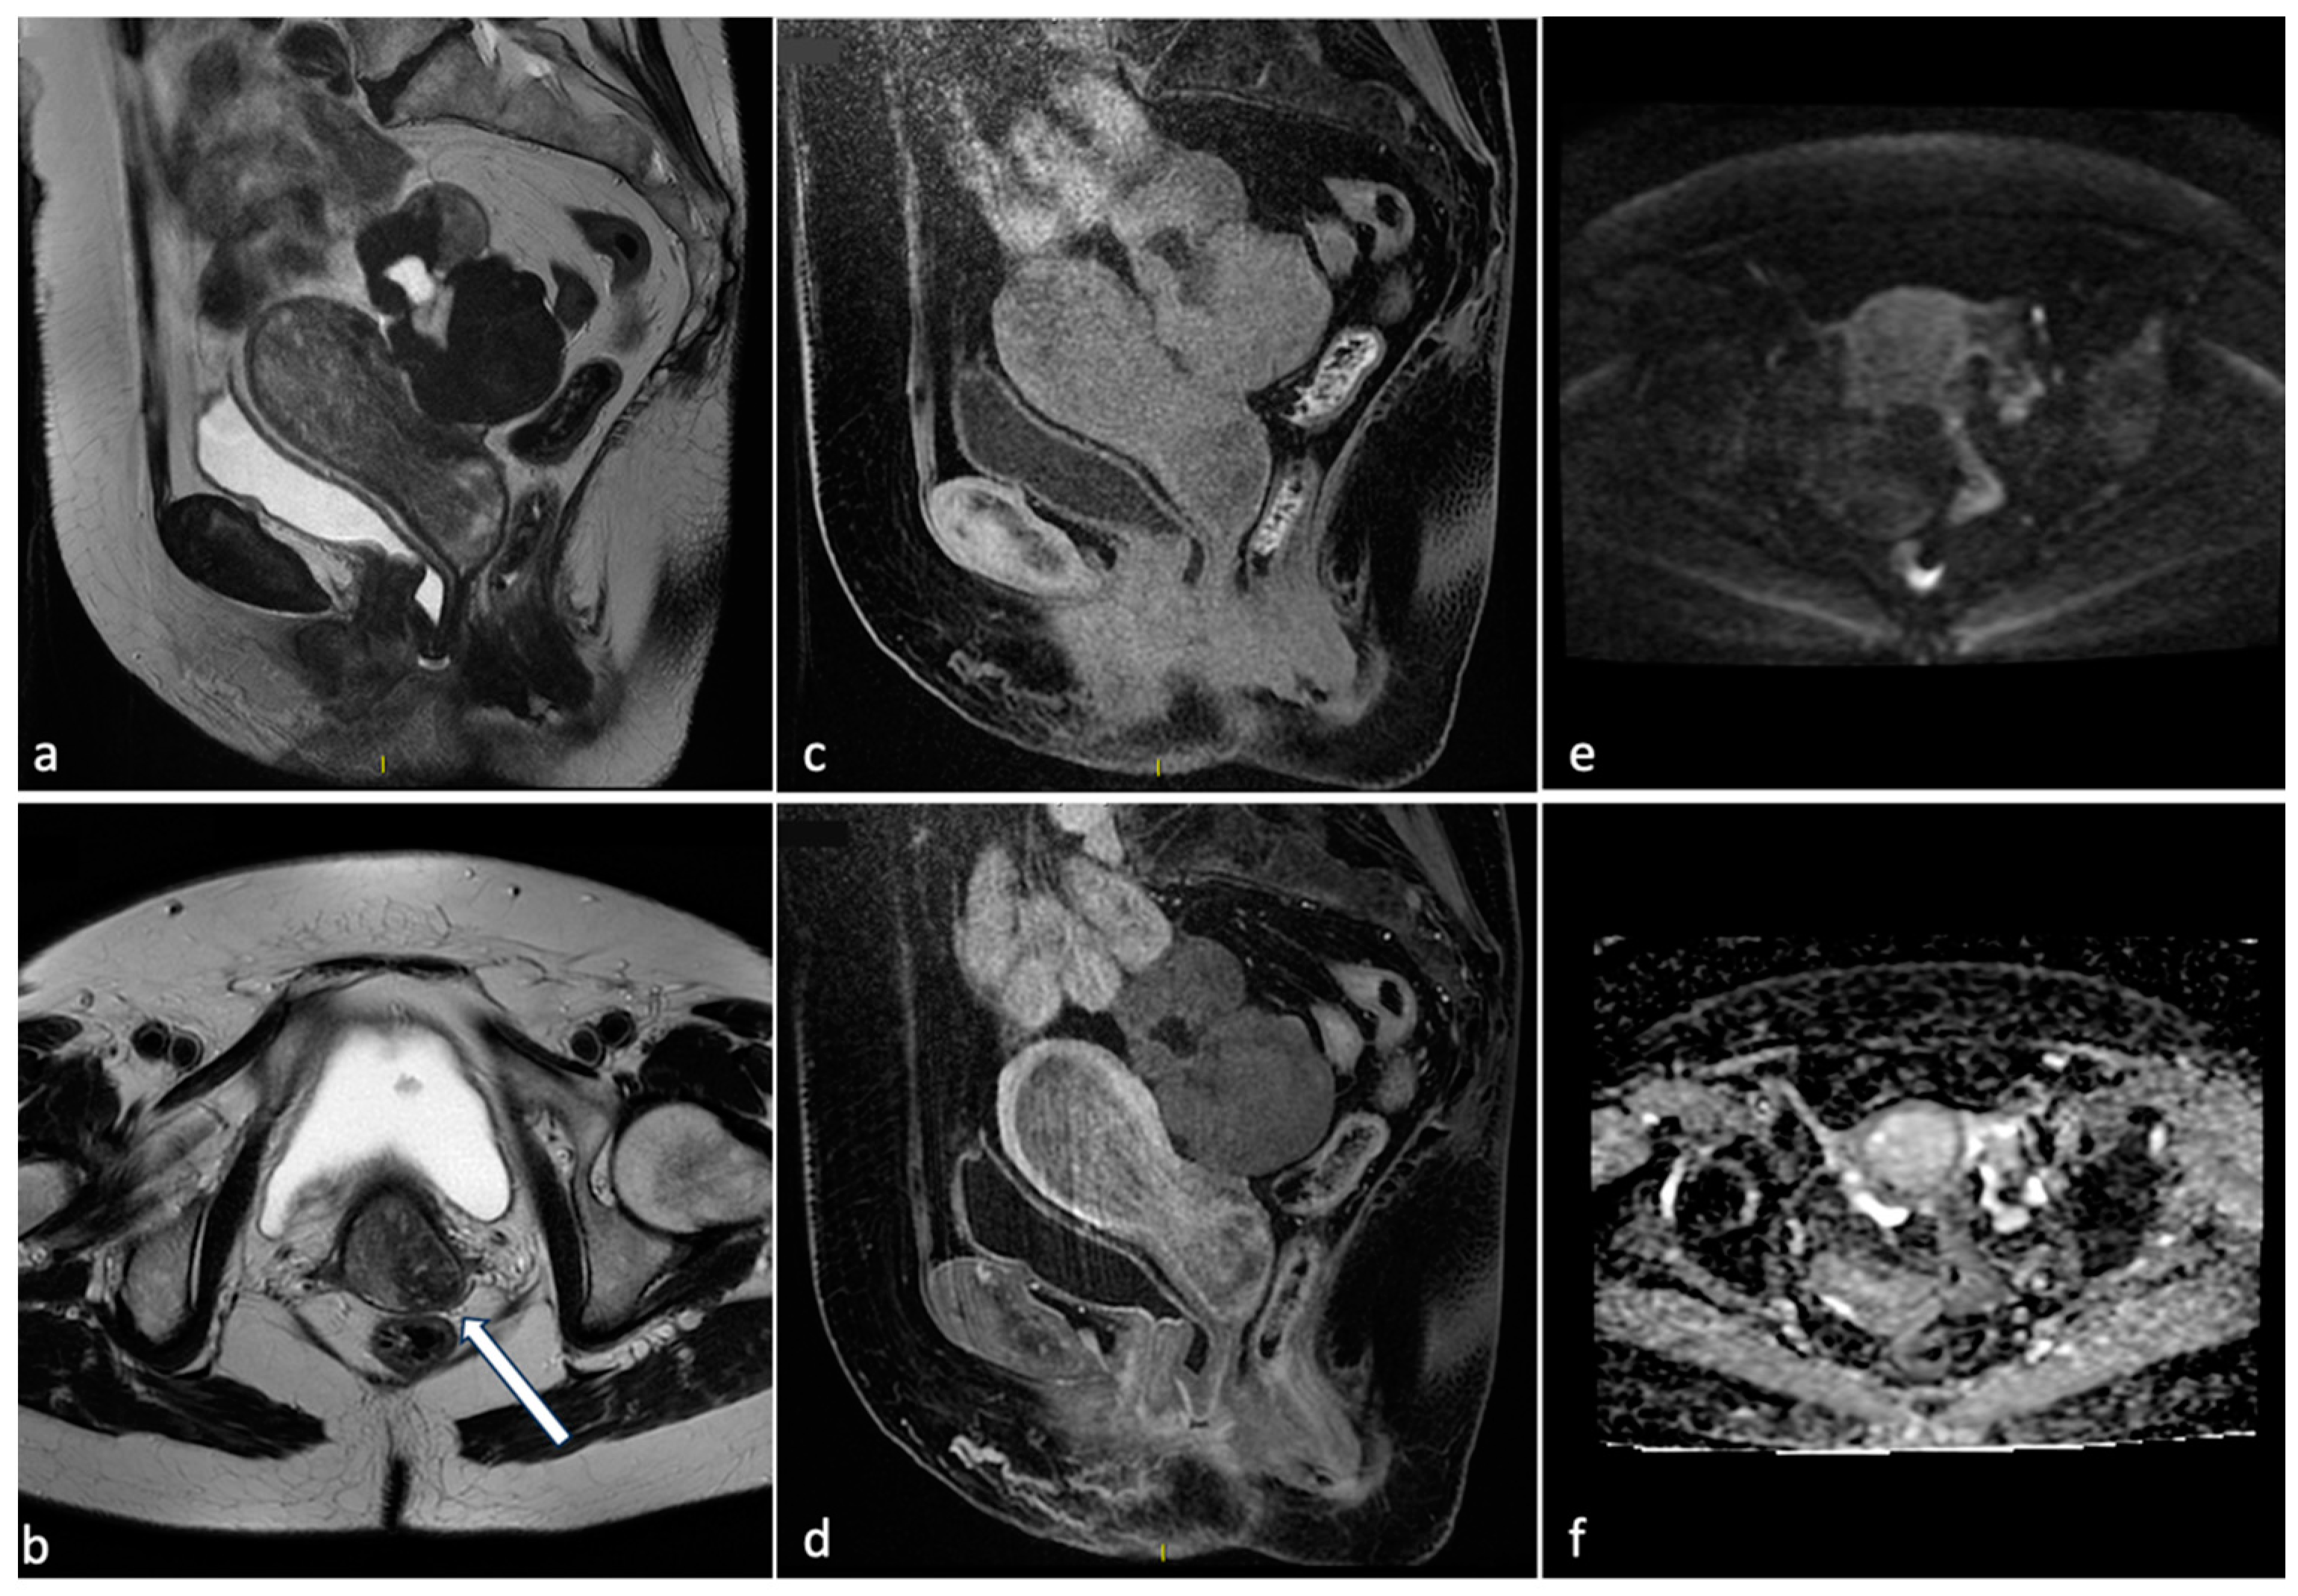

Figure 1.

Voluminous endometrial polyp. A 76-year-old woman with post-menopausal bleeding. MRI shows on T2 sequences (a,b) a voluminous mass within the endometrial cavity of intermediate signal intensity with cystic components and a fibrous core (arrow). The mass demonstrates absence of endometrial invasion on pre- and post-contrast T1 sequences (c,d) and low signal on DWI with high signal on the ADC map (e,f). These findings are suggestive of partially expelled endometrial polyp.